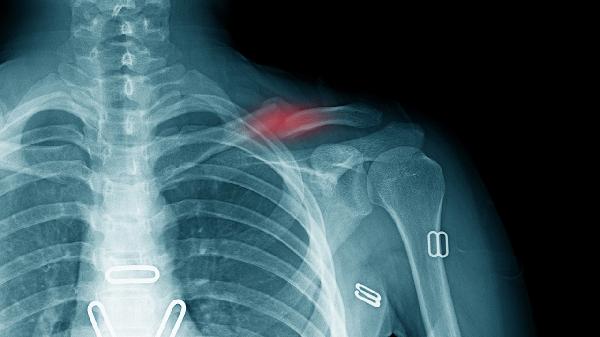

针对移位明显或不稳定性骨折。通过手术暴露骨折端进行解剖复位,使用钢板螺钉或髓内钉等内固定器材固定。术后早期需进行保护性负重,内固定物一般需在骨折愈合后1年左右取出。